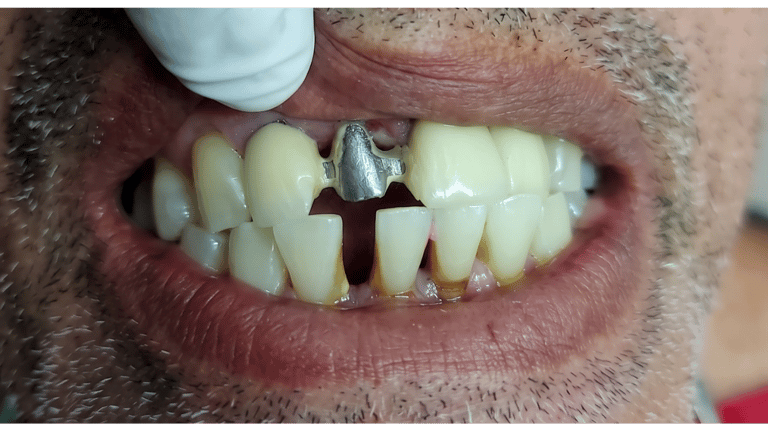

Rehabilitación Fija y Estética Cerámica

Confeccionamos prótesis metal-cerámica y sistemas libres de metal mediante estratificación artesanal capa por capa. Logramos el croma, la luminosidad y la translucidez exactas que sus casos de alta exigencia estética demandan, garantizando restauraciones que se mimetizan de forma natural en la cavidad oral

Nuestros Trabajos